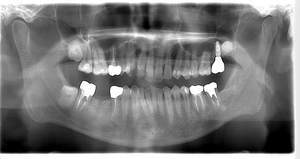

インプラント治療の症例4

レントゲン写真

- Befor

- After

口腔内写真

| 年齢 | 50代・男性 |

|---|---|

| 主訴 | 部位:左下6番7番 主訴:左下奥歯腫れて痛い。 |

| 治療内容 | 左下6番抜歯、左下6番7番骨造成、インプラント埋入 |

| 治療費 | 合計:1,232,000円 ・内訳 診断料:55,000円 サージカルガイド2本:66,000円 GBR:110,000円×2本 埋入料:165,000円×2本 静脈内鎮静麻酔:77,000円 2次OPE:22,000円×2本 仮歯:55,000円×2本 上部構造(フルジルコニア):165,000円×2本 (2023年1月現在) |

| 治療期間 | 約8ヶ月 |

| リスク・副作用 | リスク・副作用 |

| 治療方針 | 元々支台歯に負荷がかかりやすいとされている延長ブリッジを抜歯し、1本単体でしっかりかめるようにインプラントを2本埋入した。骨吸収も進んでいたため、※GBR法で骨造成を同時に行った。 治療と並行して、全顎的な歯周病治療も行い、今後は歯周病が進行しないよう、こまめにメンテナンスに通っていただく。 |

| 特記事項 | ※1 GBR・・・骨再生誘導法。骨の高さや厚みを人工骨や人工膜などを使用し再生する方法 |

| 担当者所見 | 6番は歯根分割された被せ物が7番の欠損部との延長ブリッジとされており、強い咬合と歯周病も相まって負荷がかかり動揺し、歯として機能しなくなったため、抜歯となった。 |